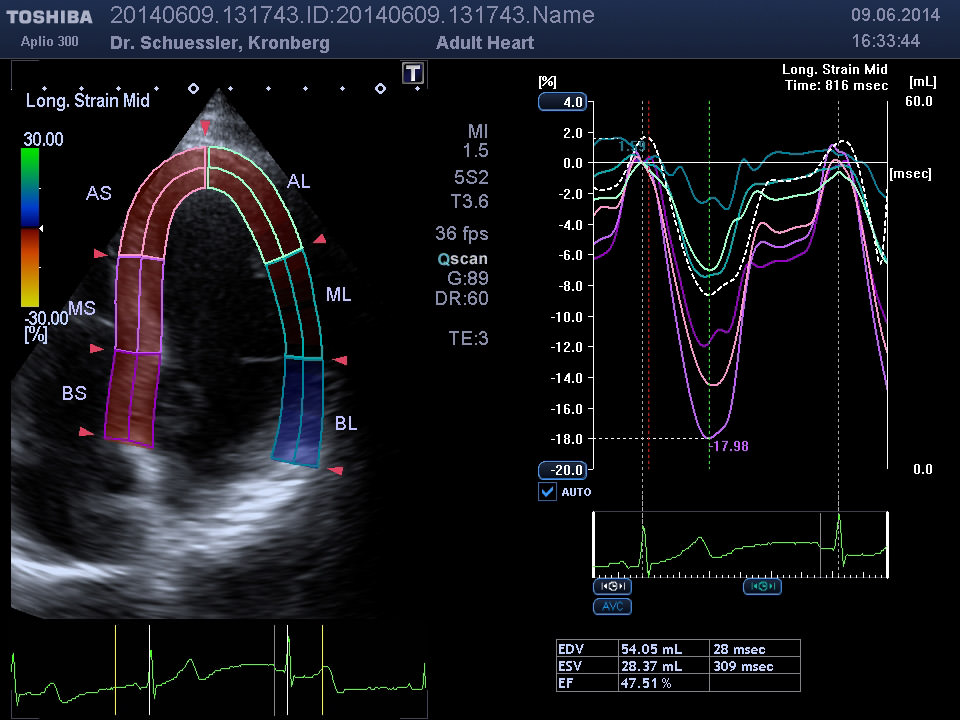

Moderne Auswertungsalgorithmen wie das „Wall Motion Tracking“ erlauben eine isolierte, hochauflösende Darstellung und Analyse der Bewegung und Funktion einzelner Segmente des Herzmuskels.

• Pumpfunktion des Herzmuskels

• Segmentale Bewegungsstörungen des Herzmuskels als Hinweis auf Durchblutungsstörungen